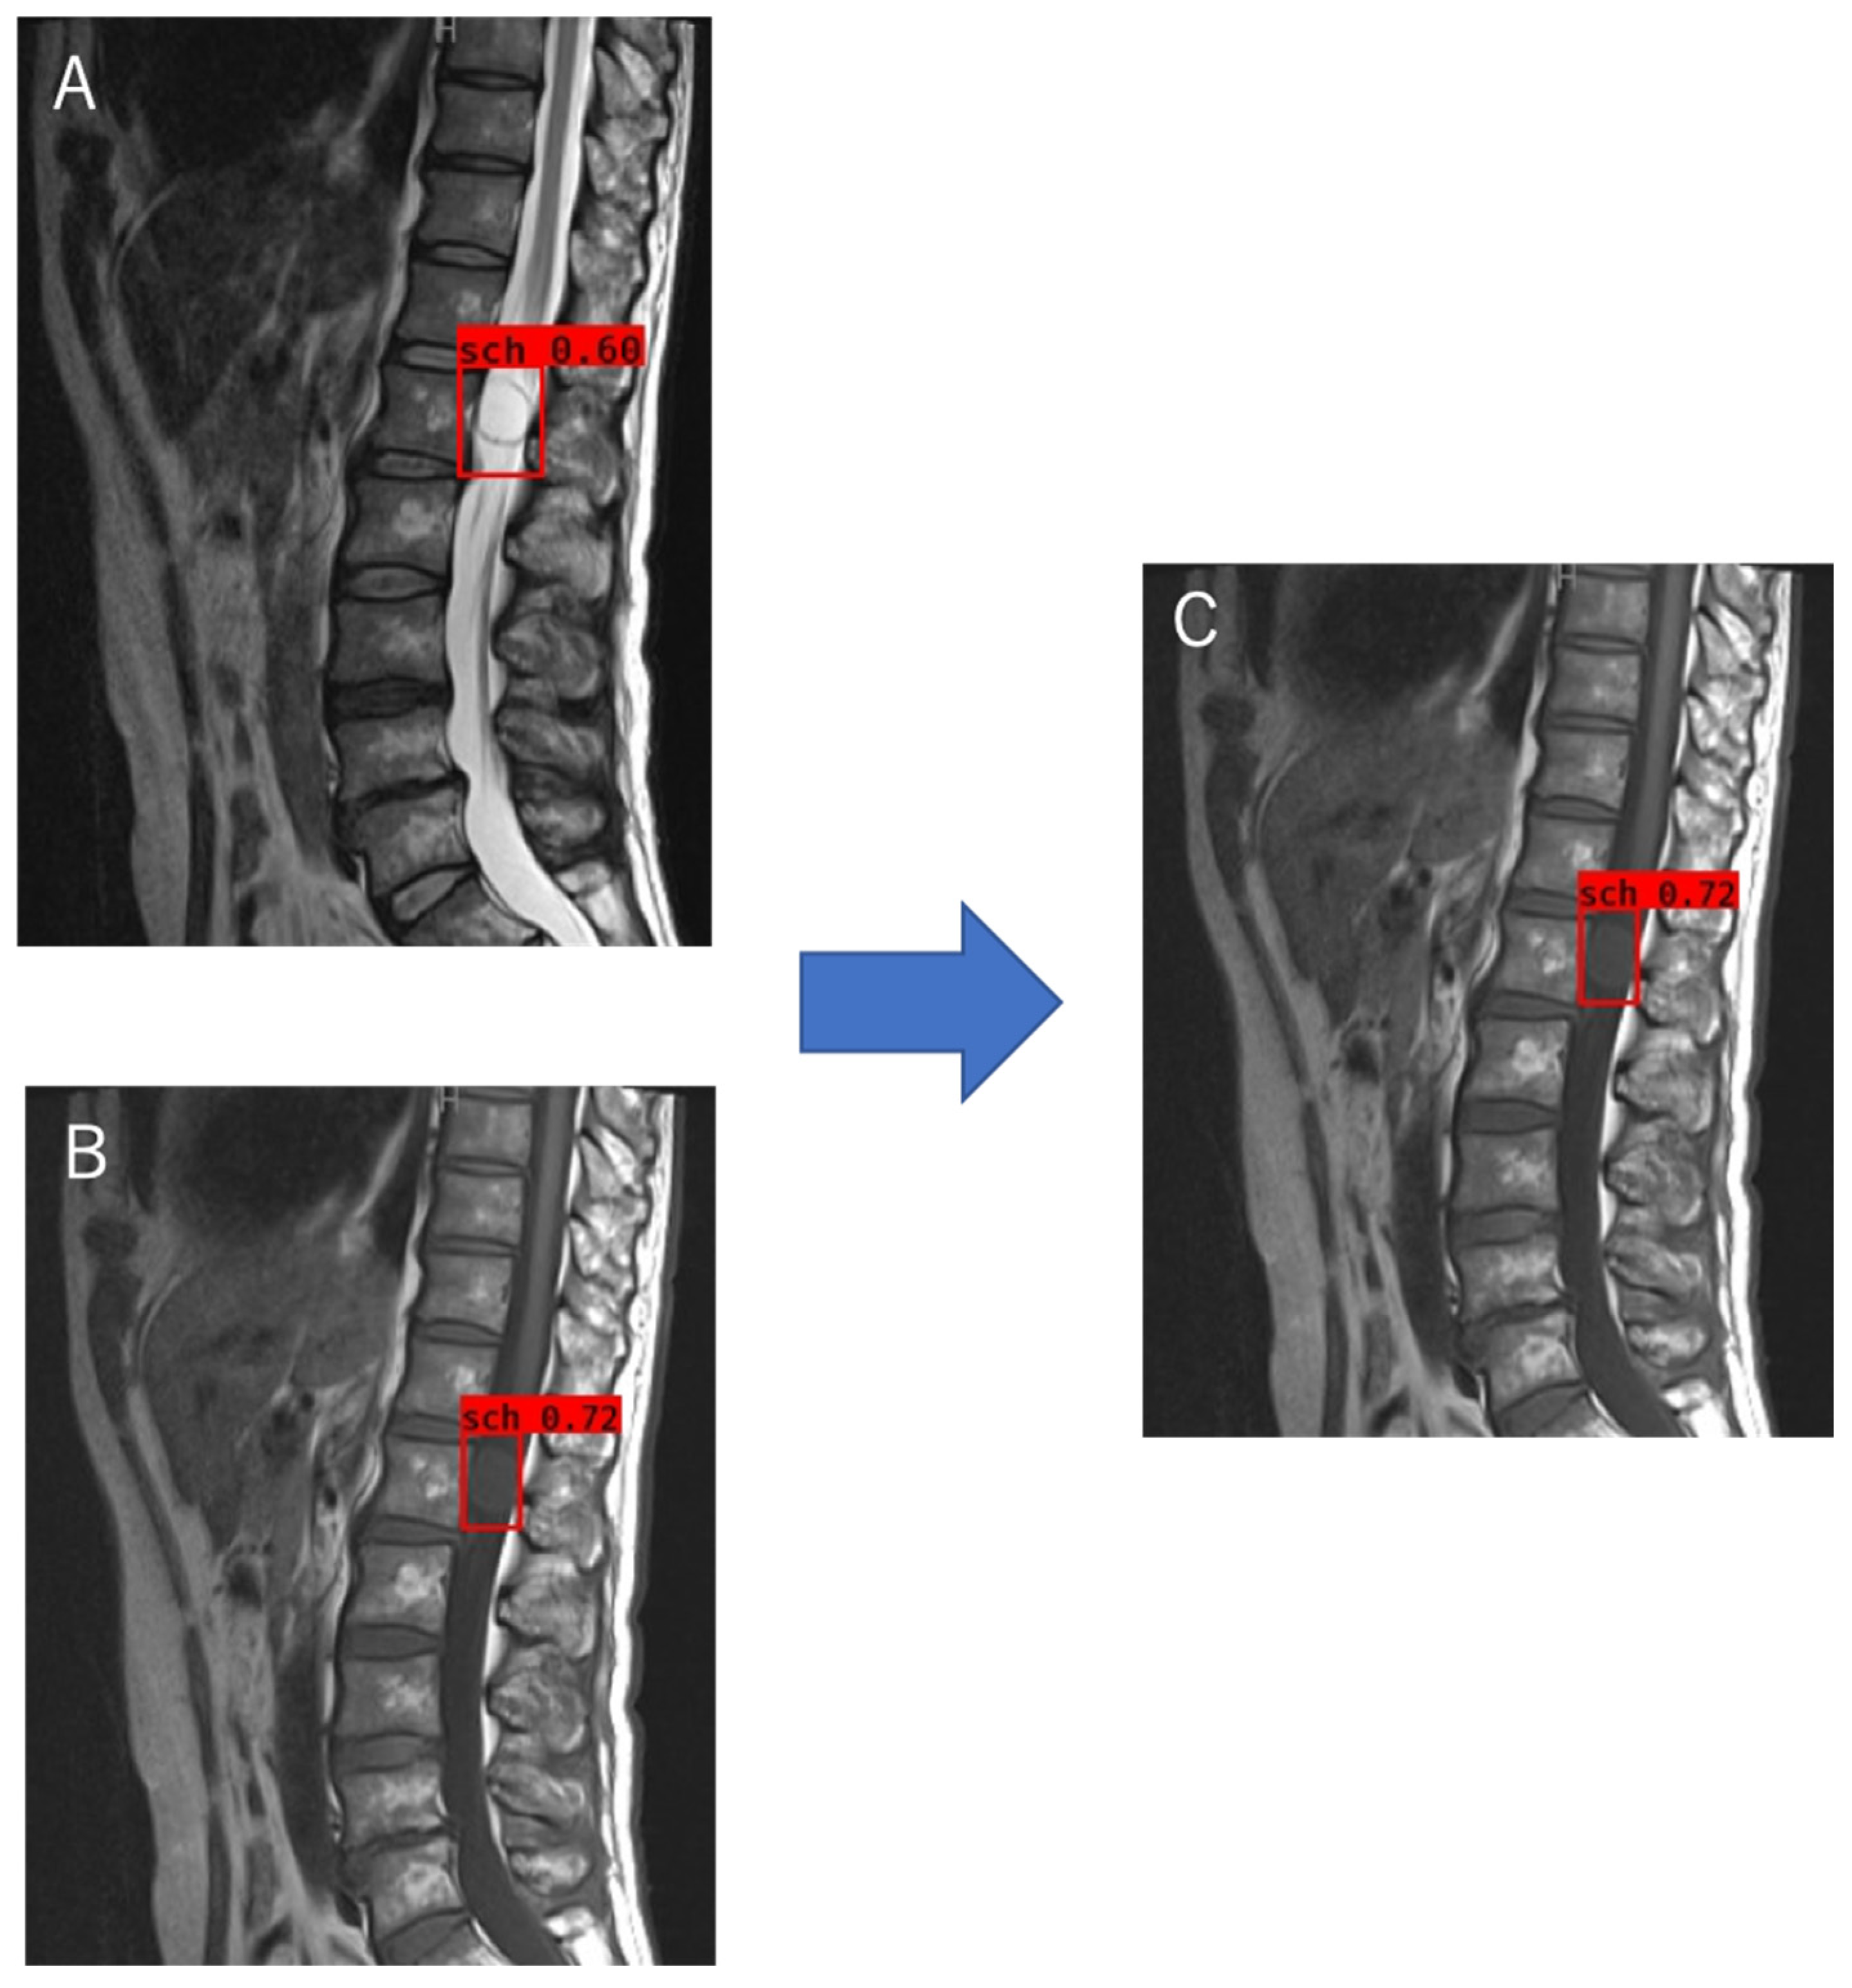

The object detection model was trained using the tumor locations and labels of the schwannomas and meningiomas as the training data. The optimal probability threshold was determined by performing a few trials. Figure 3A is an example of a T2WI MRI image of a schwannoma that was tested. A region with a probability exceeding the determined threshold was detected (Figure 3B). When multiple regions were detected during trained object detection, the region exhibiting the maximum probability was chosen (Figure 3C). For classification, we labeled the schwannomas red and meningiomas blue (Figure 3C,D), and trained the object detection model using T1W and T2W images separately. Object detection and classification achieved using T1WI and T2WI could identify the region with the highest probability achieved by using T1WI and T2WI separately (Figure 4). The object detection model was trained and validated using a computer equipped with a Quadro P6000 graphics processing unit (NVIDIA, Santa Clara, CA, USA), Xeon E5-2667 v4 3.2 GHz CPU (Intel, Santa Clara, CA, USA), and 64 GB of RAM.

Figure 3. Object detection and classification method. (AC) Process of object detection for the T2WI MRI image of a schwannoma; (A) T2WI; (B) The regions above the probability threshold were detected by the trained object detection model using T2WI; (C) The final region with the highest probability shown in (B) was selected and classified as a schwannoma; (D) The result of object detection for the T2WI MRI image of a meningioma, T2WI, T2-weighted imaging.